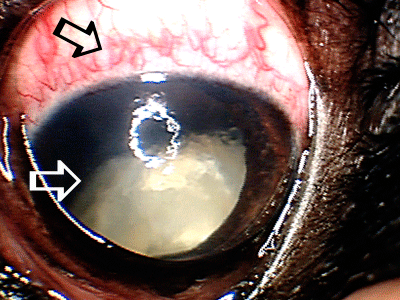

Cataract complications – chronic presence of cataracts may result in many complications resulting in the pain, discomfort and eventual need for the surgical eye removal. This patient had long standing cataract (white arrow), which resulted in glaucoma (elevation of intraocular pressure) resulting in ocular pain, redness (black arrow) and eventual need for the surgical eye removal.

Cataract complications – chronic presence of cataracts may result in many complications resulting in the pain, discomfort and eventual need for the surgical eye removal. This patient had long standing cataract (white arrow), which resulted in glaucoma (elevation of intraocular pressure) resulting in ocular pain, redness (black arrow) and eventual need for the surgical eye removal.